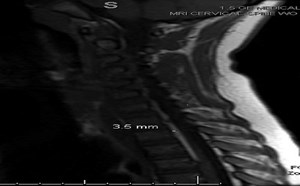

3rd Place Emage Winner: A Case of Neck Pain